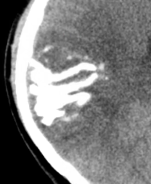

Oligodendrogliome (grade II)

- Comme un astrocytome diffus mais 1p19q co-déletion

- Calcifications ++

- Parfois kystes

Oligodendrogliome anaplsaique (grade III)

- Comme un astrocytome anaplasique mais 1p19q co-déletion

- Calcifications

- Kystes

cerebrales cerebrale tumeur oligo dendro dendrogilome oligodendrogliome